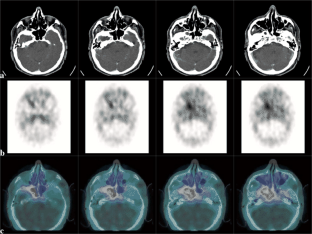

Abb. 3 a–c: